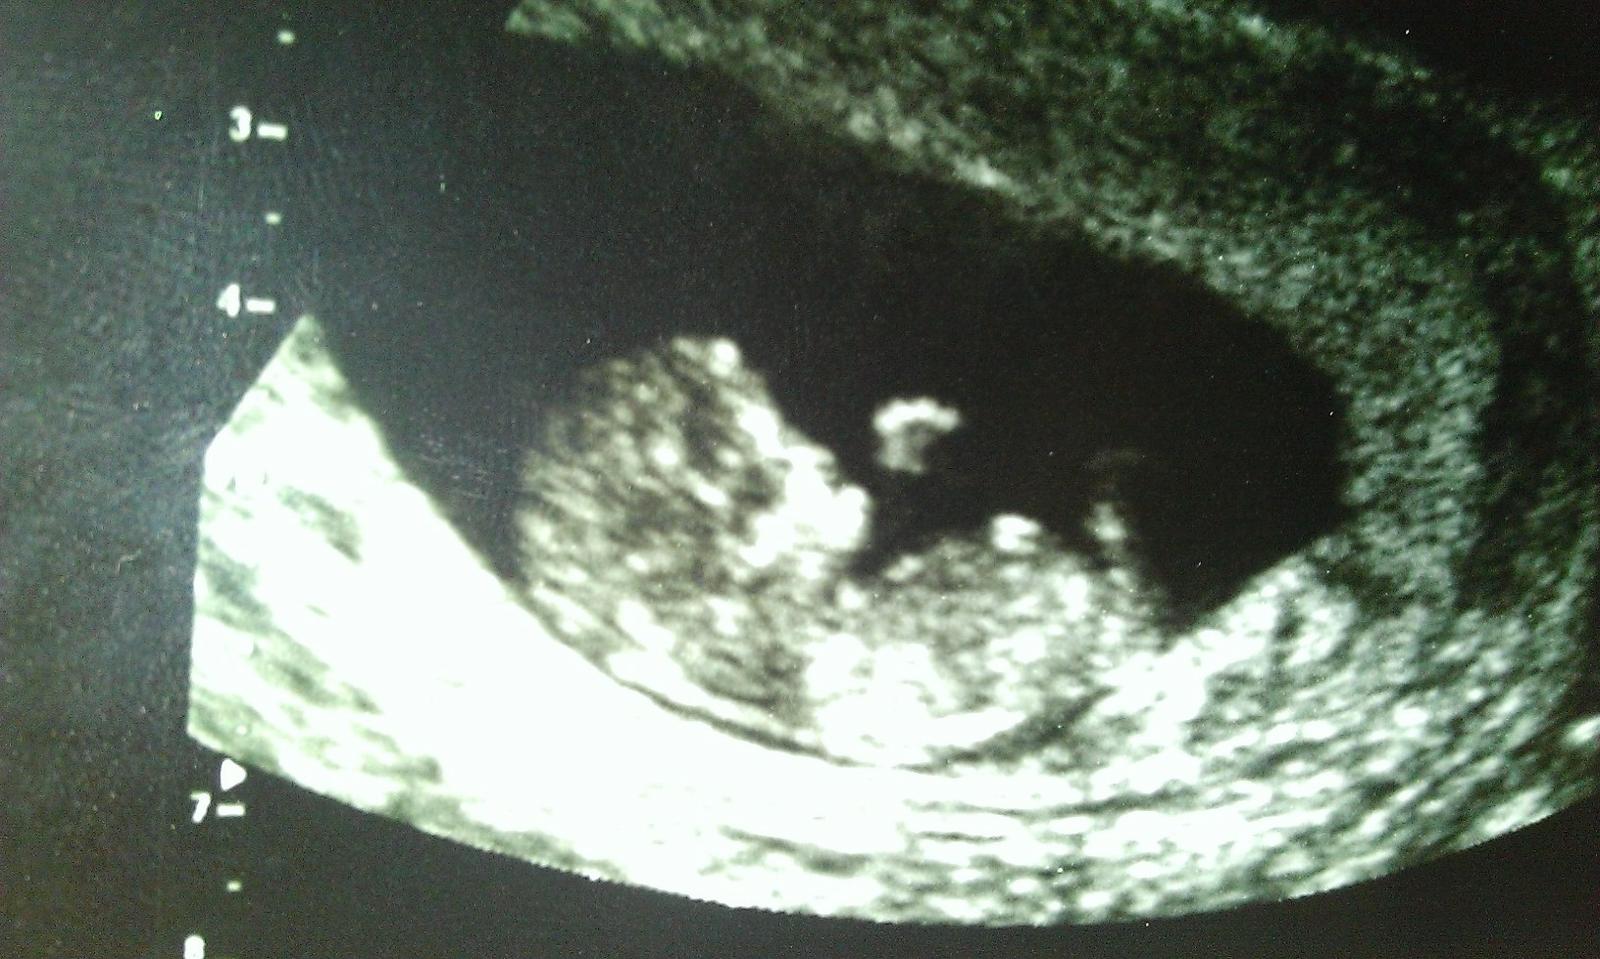

@beru3nek @ivanaliana ahojte babuleee 🙂 tak vsetko je v poriadku, drobcek ma 8cm a srdiecko mu veselo bije 🙂 juuuj taka som stastnaaaaa 🙂 na screening idem 21.2. 🙂

babule opravujem tu dlzku, lekar mi dlzku nepovedal, povedal len ze dlzka zodpoveda tyzdnu, ze je to v poriadku, a ja som tych 8.0cm vycitala z fotky, tam je to napisane... ale jedna babula na inom fore mi povedala ze to nie je dlzka babatka... ale tak to je jedno, hlavne ze je to ok 🙂

@lienka19881 Lenusik...to je naaaaaaadhera...mormalne mi vyhrkla slzicka ked som to zbadala 😅 ...Ako si tam krasne lezka babenko nadherne a ta rucinka malinka...no umriem.To je fakt zazrak toto

@ivanaliana ja som mala tiez slzicky v ociach ked som to dnes videla... Este mi lekar hovori ze aha prave vam kyve rucickou 🙂 no skoro som sa tam rozplakala... Uplne nadherny pocit 🙂uz sa tesim na tvoju pondelkovu fotecku 🙂

@lienka19881 : jé, nádhera. Krásnej bobeček, už hotový miminko, co. I to bříško hezky vypapaný. No 8 cm je asi hodně, já měla 2.5 cm v 9 tt, tak to by tak asi nevyrostlo. No super. Já jdu na screening den po tobě 😉

@beru3nek uz mi aj baby povedali ze 8 cm bude nieco ine 🙂 ale povedal ze velkost zodpoveda tyzdnu, takze som rada 🙂 je to uz hotove male babo, aj prstiky mu vidno 🙂 neboj, jasne ze je vsetko ok, ja uz ani jeden priznak a mimi sa ma dobre 🙂 nech uz je radsej to zari (september??? 😀 )